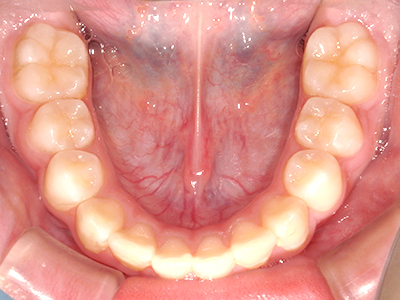

歯並びの相談に来られるお子様は、口呼吸をしているケースが多く、これが歯並びに大きな影響を与えています。

- 口呼吸をしている

↓ - 舌の位置が悪くなる

↓ - 頬の圧力が上の歯列にかかりやすくなる

↓ - 上あごが狭くなる

↓ - 下あごが狭くなる・下あごの位置が悪くなる

↓ - さまざまな不正咬合が生じる

ないき歯科クリニックでは、上あごの成長不足を補い、鼻呼吸を獲得しつつ歯列を整え、将来のお口をより健康な状態にすることをゴールに定める矯正治療をおこなっています。